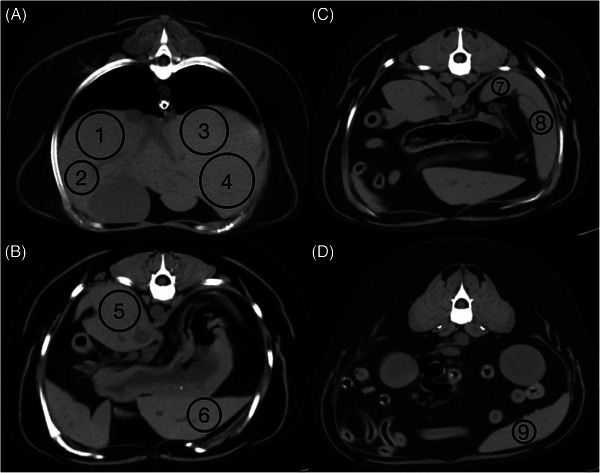

Hypoattenuation of the liver, consistent with hepatic steatosis or lipidosis, has been reported in veterinary patients. In people, measuring CT hepatic attenuation is diagnostic for hepatic steatosis, and hypoattenuation of the liver is defined as absolute if less than 40 HU or relative if the liver is 10 HU less than the spleen. The purpose of this study is to describe hepatic parenchymal attenuation in dogs with diabetes mellitus with or without diabetic ketosis (DK) or diabetic ketoacidosis (DKA), using the above categorization for absolute and relative hypoattenuation, as with humans. We hypothesized dogs with DK or DKA were more likely to have hypoattenuating livers. Twenty-seven diabetic dogs were included; fifteen were categorized in Group 1 as without DK or DKA, six in Group 2 as DK, and six in Group 3 as DKA. In Group 3, four of six dogs had absolute and relative hypoattenuating livers. Three of these were visually hypoattenuating to the vasculature, with one having negative attenuation and a histopathologic diagnosis of severe hepatic lipidosis. In Group 2, four of six dogs had relative hypoattenuating livers. In Group 1, only one of 15 dogs had a relatively hypoattenuating liver. Groups 2 and 3 had significantly lower absolute liver attenuation than Group 1. Presumed hepatic steatosis was present on CT and was more common with DK or DKA. These findings may help provide hepatic sampling recommendations and alter patient prognosis. Further research is needed to establish absolute and relative liver attenuation in dogs with correlation to histopathology and patient outcome.